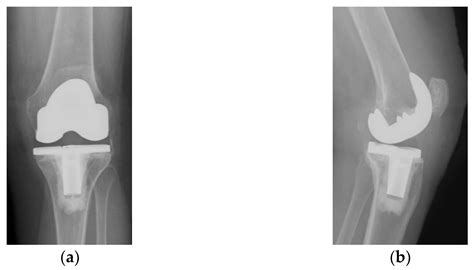

• Exposure: How the surgeon makes the incision to access the damaged joint surfaces.

• Resurfacing: The precise removal of damaged cartilage and bone from the femur and tibia.

• Implant Placement: Securing the metal and plastic components that act as the new joint.

Many patients worry about pain management, the appearance of the surgical site, and the longevity of the implant. By watching a professional Total Knee Replacement video, you can witness the precision involved in modern robotics-assisted surgery, which often leads to smaller incisions and more accurate alignment. This knowledge helps address common misconceptions, such as the idea that the entire knee is “replaced.” In reality, the procedure is more of a resurfacing of the joint, where only the diseased bone and cartilage are removed and replaced with high-durability prosthetic materials.